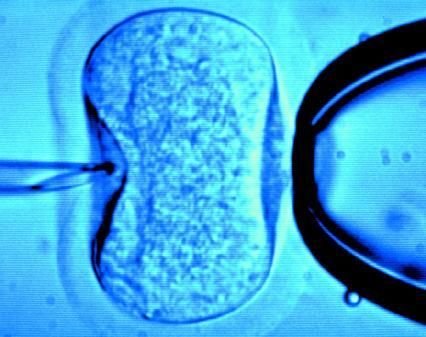

60歲老婦將成為英國接受試管受精最年長者(圖)

據英國《每日郵報》1月18日報道,英國一位60歲老婦將成為英國接受試管受精最年長者。這位老婦名叫蘇珊·托勒夫森,是一位退休教師,到今年10月她就滿60歲了。2008年,蘇珊曾去俄羅斯接受試管受精,在英國生下了她的第一個孩子。

倫敦哈利街的私人診所是英國試管嬰兒手術成功率較高的醫院之一,醫生們在上周一同意幫助蘇珊·托勒夫森進行第二次人工受孕。通常情況下,私人診所只在特殊情況下給50歲以上的婦女進行試管受精,例如,患者仍然有月經周期。這件事引起了絕經后婦女是否有生育權利的倫理大討論,現在要求提高生育治療年齡上限的呼聲越來越高。